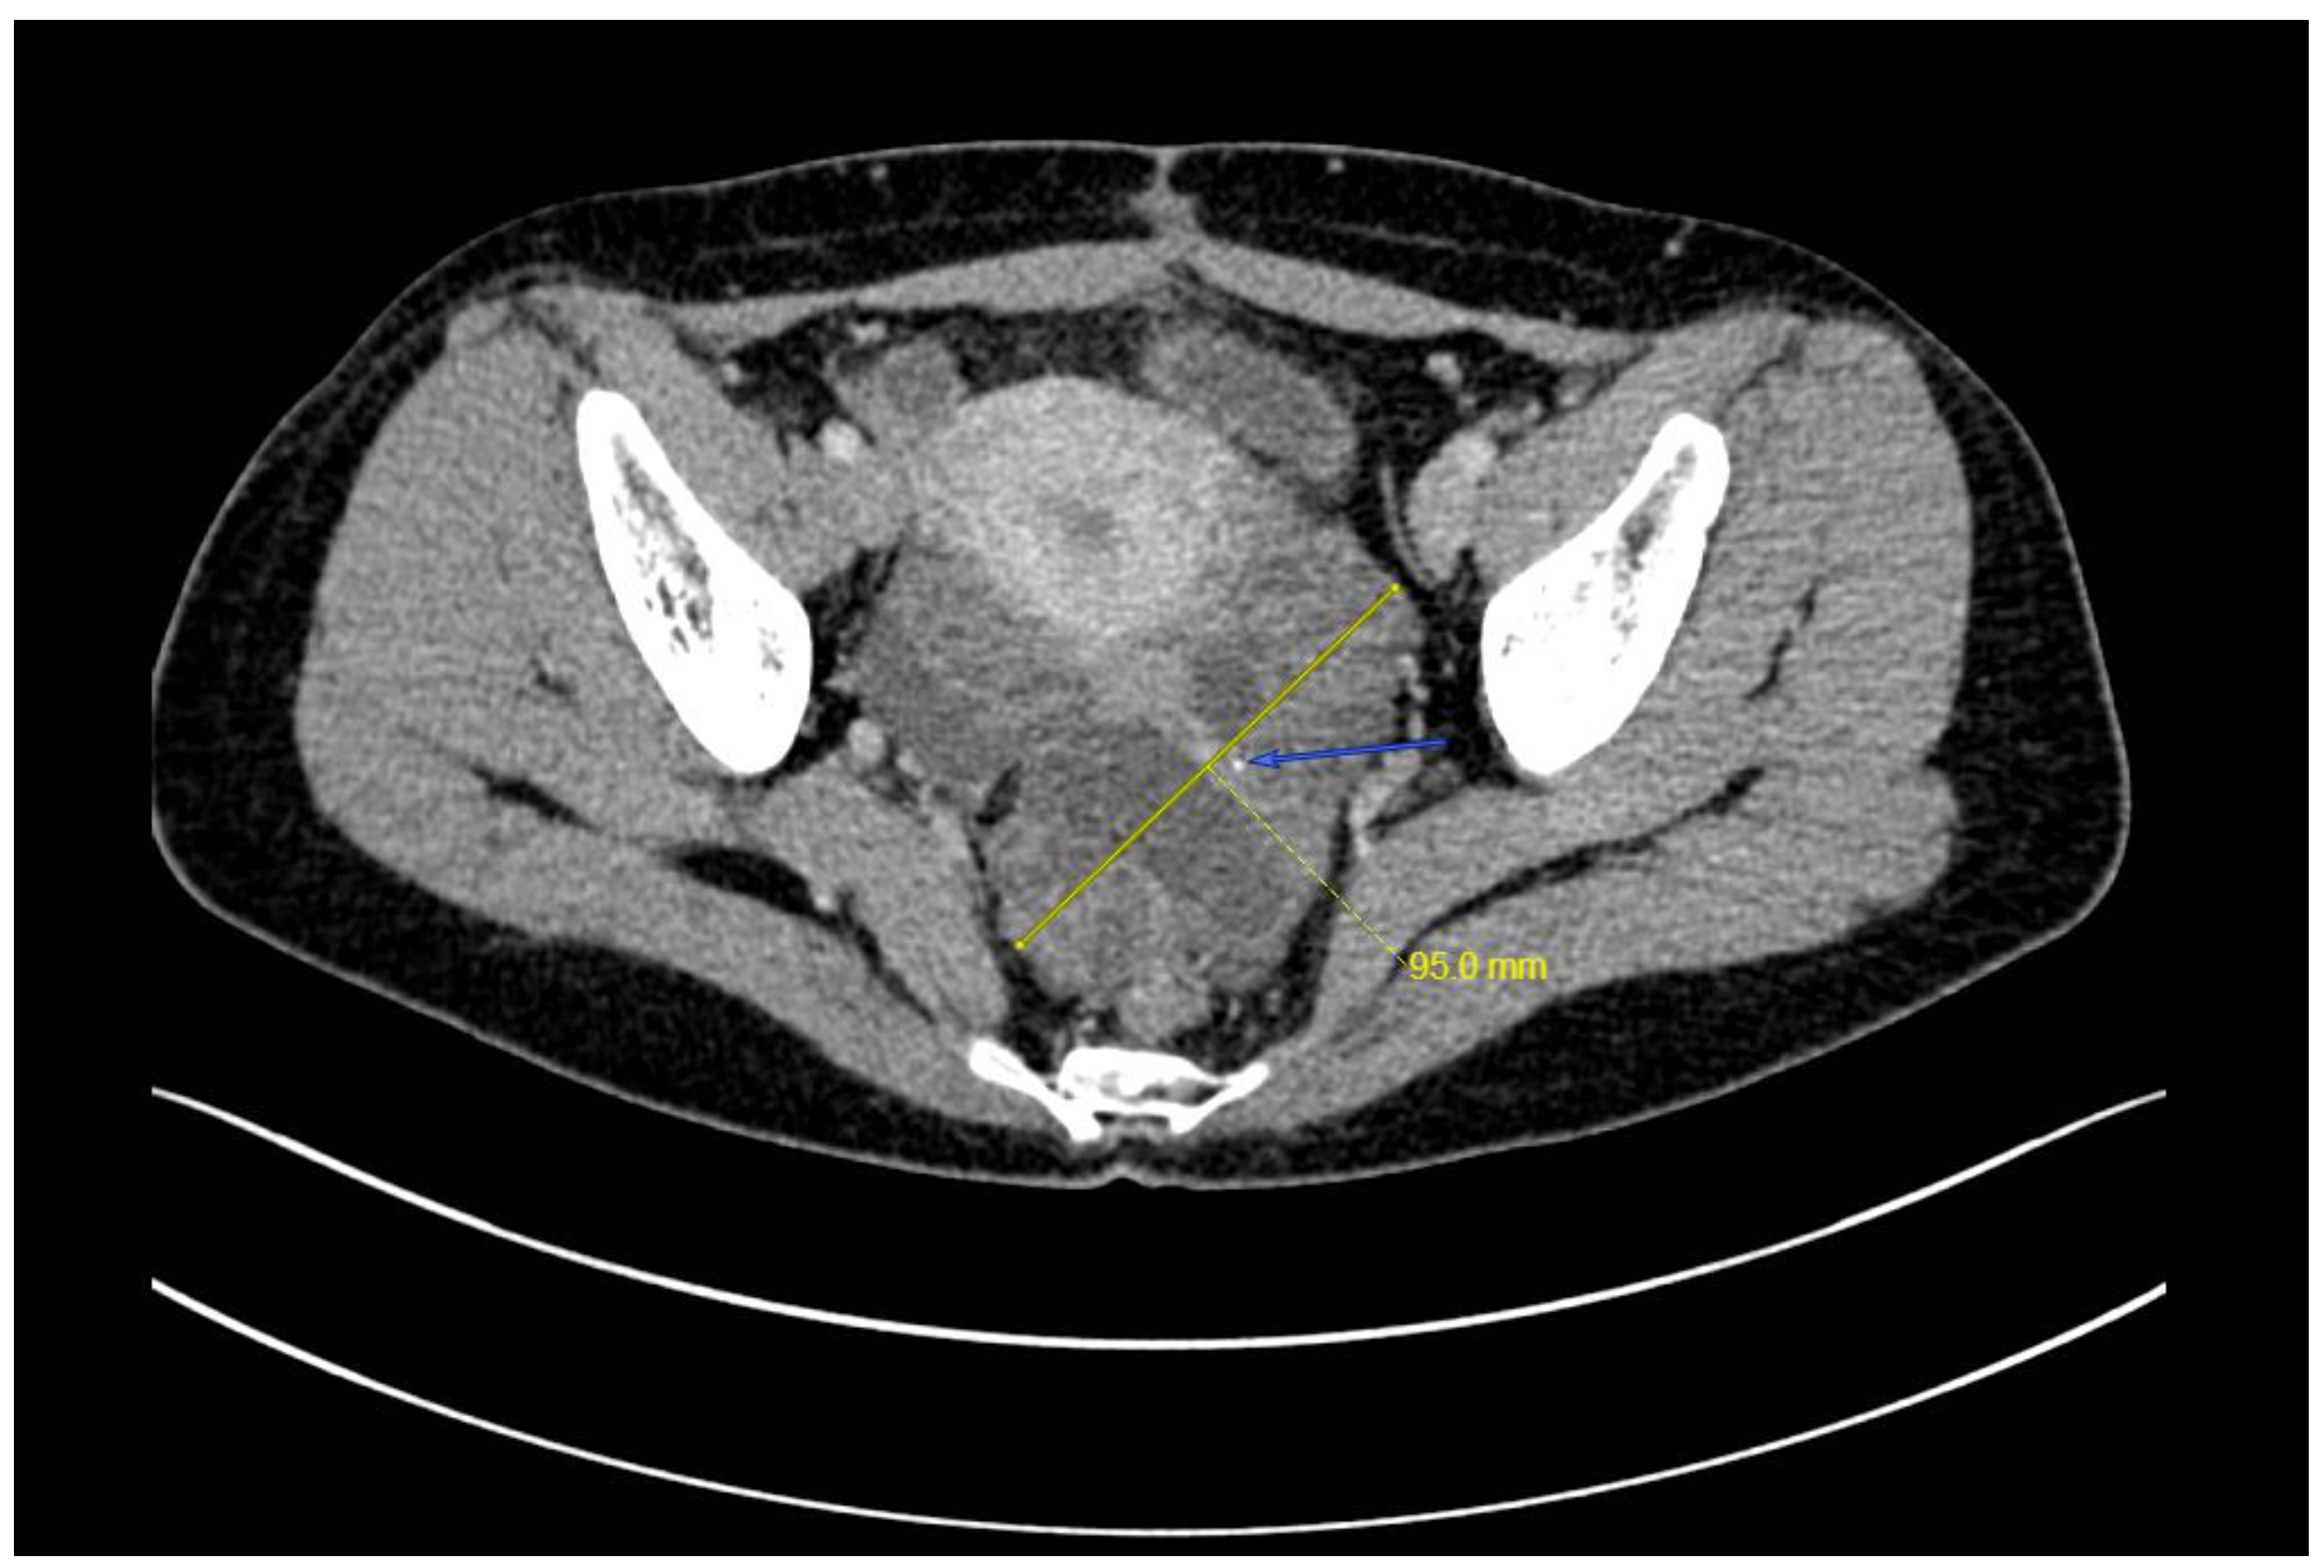

2. Case